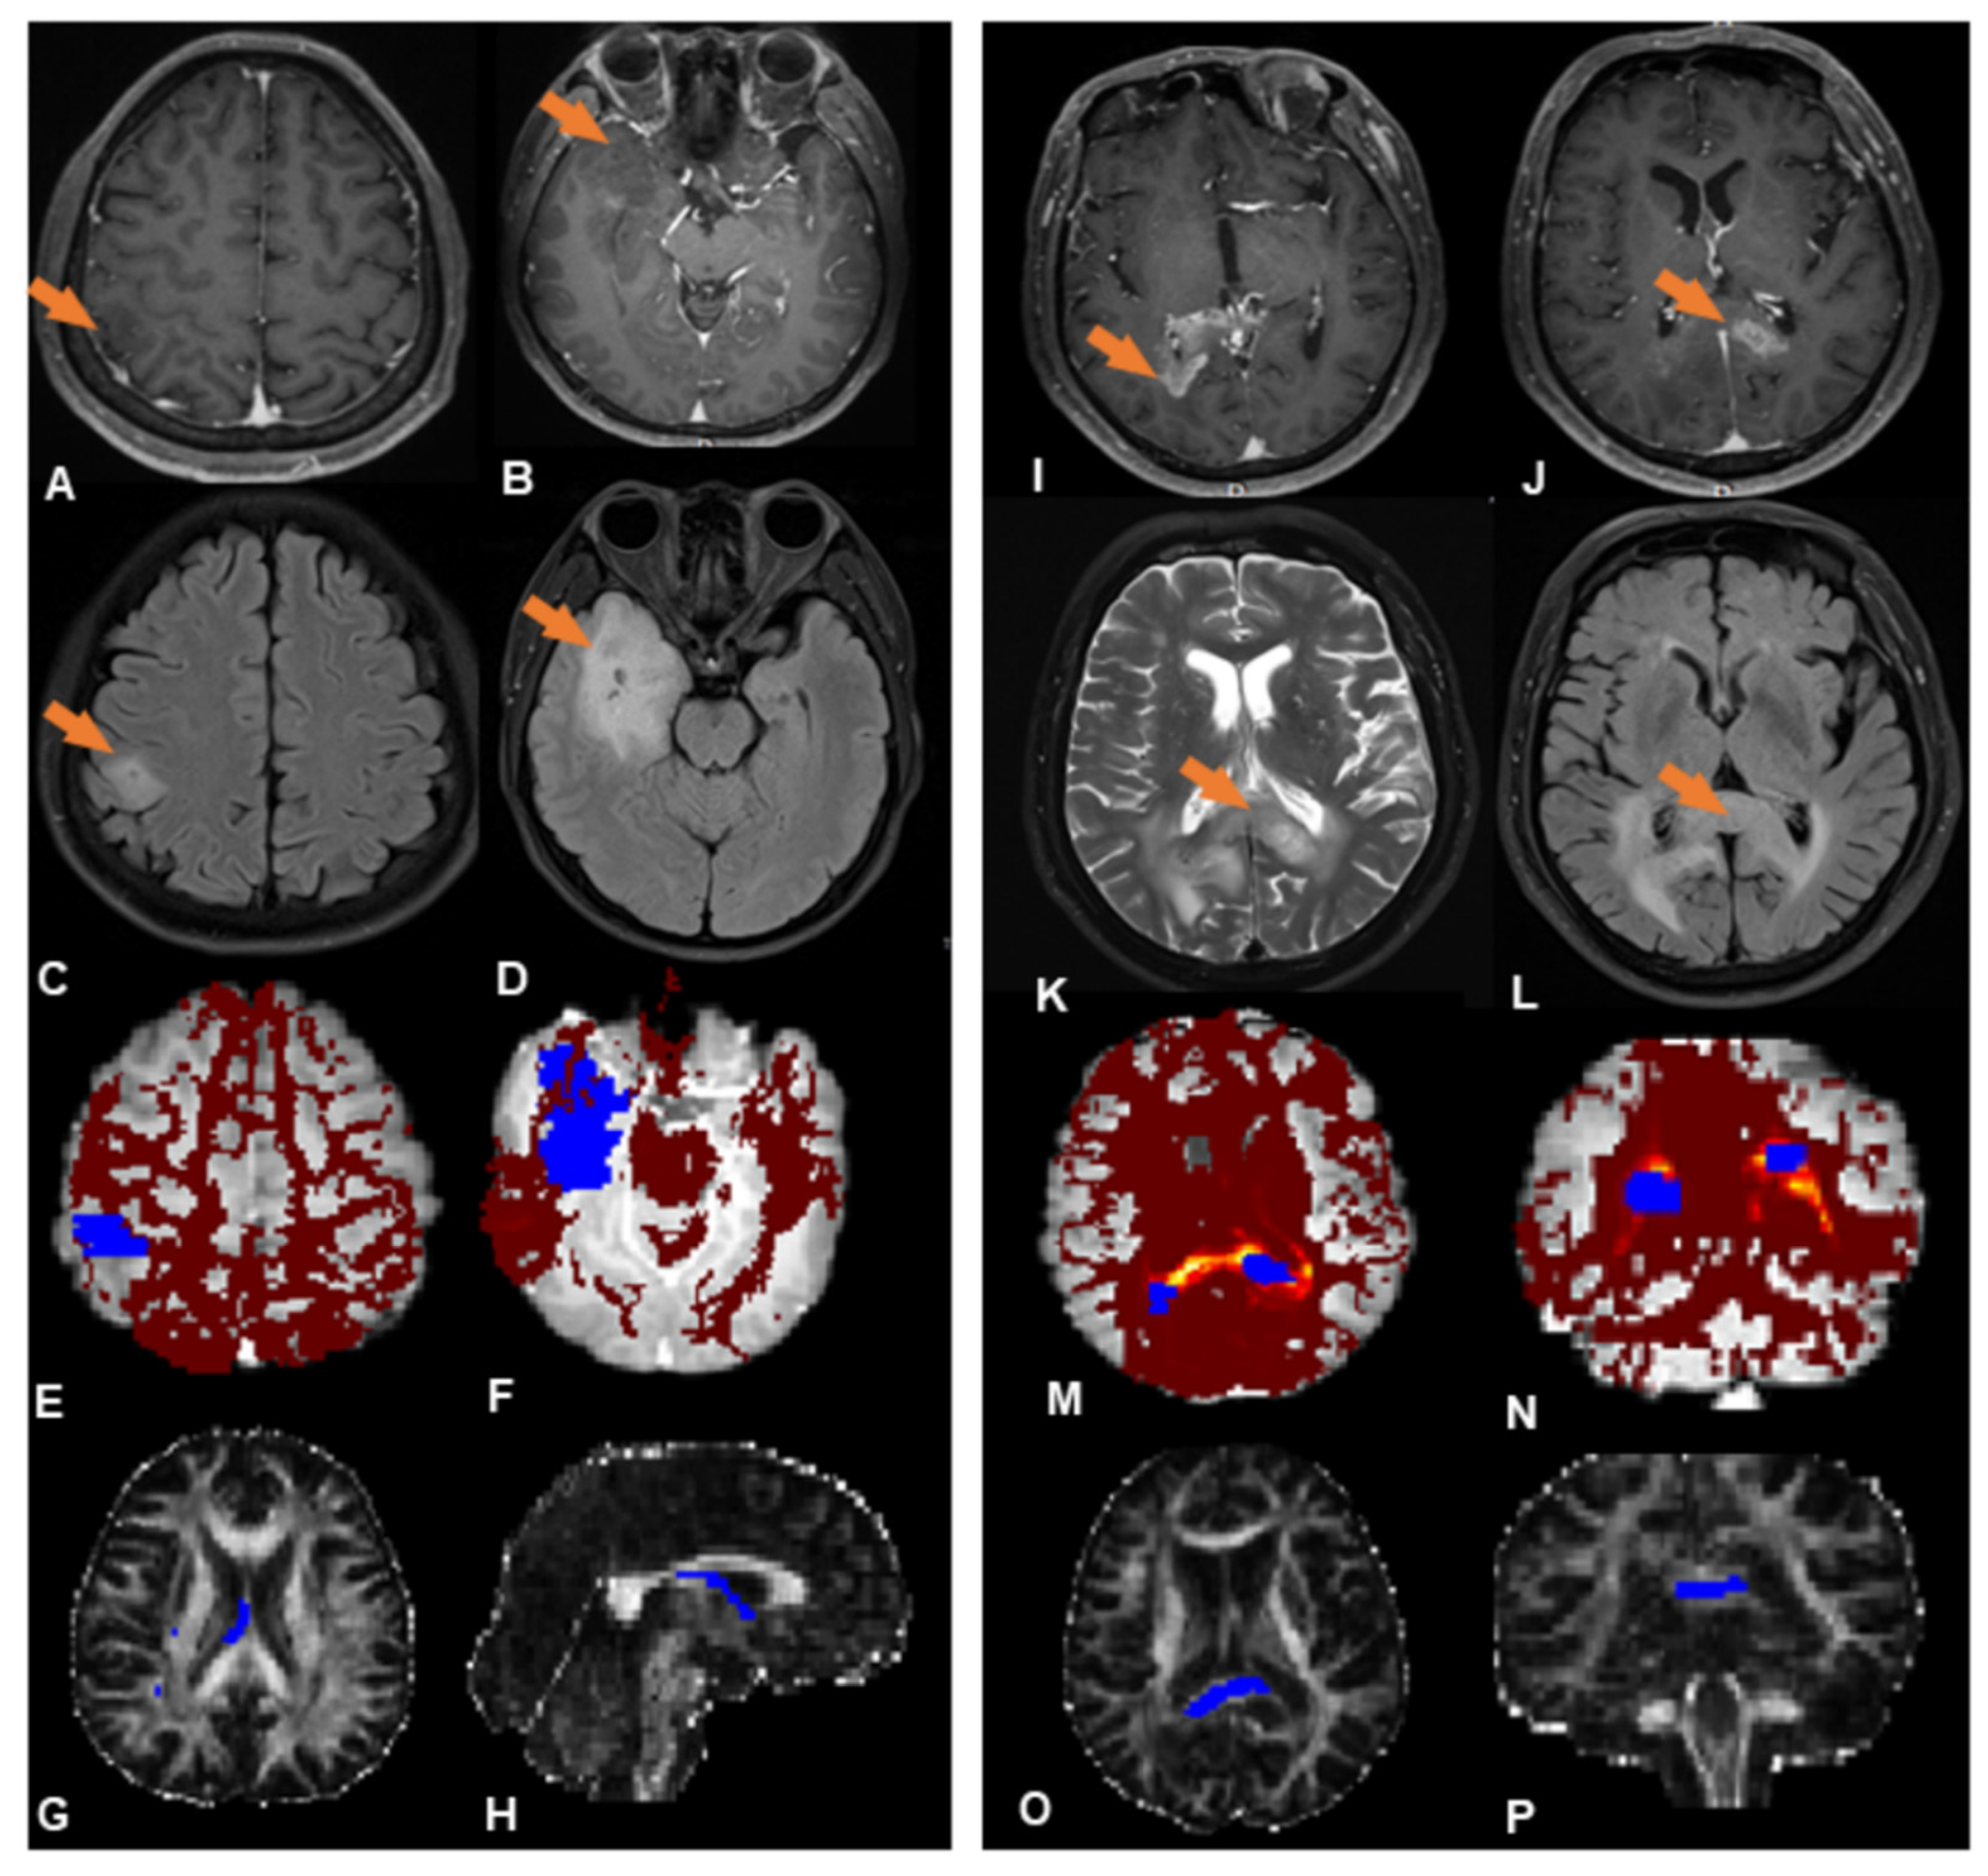

3.2. Probabilistic Fiber Tracking

3.3. Hierarchical Clustering

3.4. Subgroup Differences

| Connectivity | 2675 ± 1098 | 30432 ± 22707 | −5.23 | p = 0.000016 * |

| FA | 0.34 ± 0.116 | 0.30 ± 0.108 | 1.15 | 0.26 |

| rCBV | 2.31 ± 0.95 | 1.73 ± 0.48 | −3.11 | 0.002 * |

| rADC | 1.32 ± 0.25 | 1.21 ± 0.27 | −1.58 | 0.12 |

| MR spectroscopy | ||||

| Cho/Cr | 0.52 ± 0.26 | 0.74 ± 0.57 | −1.49 | 0.14 |

| NAA/Cr | 0.96 ± 0.62 | 0.77 ± 0.41 | −1.43 | 0.14 |

| Cho/NAA | 1.07 ± 0.54 | 1.34 ± 0.42 | −1.49 | 0.13 |

| Lip/Cr | 0.32 ± 0.22 | 0.060 ± 0.051 | −2.71 | 0.006 * |

| Lac/Cr | 0.62 ± 0.85 | 0.45 ± 0.32 | −0.72 | 0.47 |